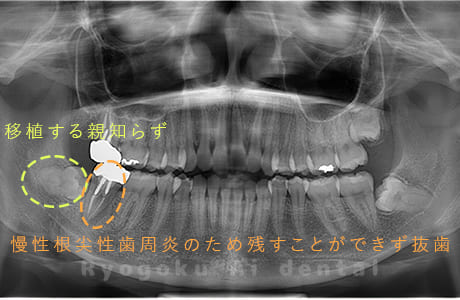

Case01

- 原因

- 慢性根尖性歯周炎

- 治療期間

- 3ヶ月

- 治療内容

- 自家歯牙移植手術+マイクロエンド+ダイレクトボンディング

- 治療費用

- ¥220,000

他院で根尖病変が大きく、抜歯と判断され、インプラント手術を提案された患者様です。親知らずが残存していたため、自家歯牙移植手術を行いました。

<リスク・副作用>

治療後、痛みや違和感、出血、腫れなどが出る事があります。喫煙者、糖尿病などの方の場合、歯が生着しない場合があります。